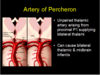

The medial & anterior nucleus of the thalamus is supplied by what arteries?

•Thalamoperforating

•Thalamogeniculate

•Inferior Thalamic

•Postero-medial choroidal

Thalamoperforating